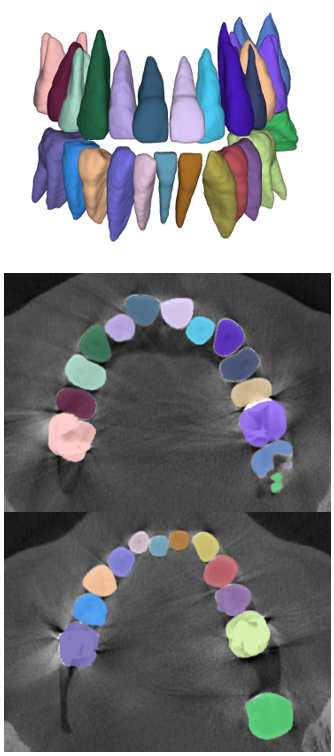

The manual seeded level-set methods [6, 7] demonstrate inferior performances while segmenting teeth with predominant metal artifacts (Table II). The energy-based (i.e., level-set function) algorithmic approach failed while defining an optimum stopping criterion (Fig. 12b). The AJI measures for level-set methods are omitted because the box detectors do not exist in the level-set-based methods. In particular, the low precision and sensitivity values indicate that level-set methods have over-segmented or under-segmented the teeth in many cases (Figs. 12b and 13a). The accuracies of the Mask-RCNN [17] and ToothNet [11] showed comparable performance to the level-set-based methods. The instance segmentation framework successfully detected and segmented the teeth automatically. However, it failed to detect all the teeth regions accurately, which resulted in a degradation of the segmentation performance. Moreover, the performance of the segmentation itself also showed low accuracy owing to the metal artifacts (Figs. 12c and 12d). Figure 13 illustrates the more severe conditions of metal artifacts. The performance of the detection and segmentation processes significantly degraded in ToothNet [11] (Fig. 13b) and Mask-RCNN [17] (Fig. 13c). Conversely, our proposed method outperformed the other state-of-the-art methods (Figs. 12e and 13d); further, the comparison between the PA- and non-PA-based results also demonstrated that the employment of a PA detector significantly improved the proposed architecture (Table II). The superior AJI value clearly shows that successful detection improved the overall performance.